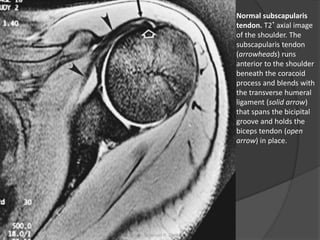

Normal subscapularis

tendon. T2* axial image

of the shoulder. The

subscapularis tendon

(arrowheads) runs

anterior to the shoulder

beneath the coracoid

process and blends with

the transverse humeral

ligament (solid arrow)

that spans the bicipital

groove and holds the

biceps tendon (open

arrow) in place.